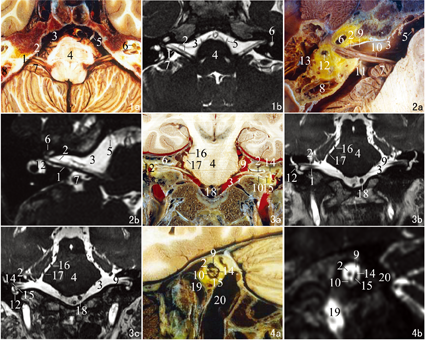

头部MR图像与连续断层标本对面神经及前庭蜗神经结构的识别具有较好的一致性,且断层标本图像的显示信息更为丰富。本研究选择了4个典型断面,观察面神经、前庭蜗神经颅内段及内耳道段的走行规律、毗邻关系及重要的识别标志。

面神经与位于前庭蜗神经的前方,后者较前者略粗大,二者自延髓脑桥沟水平发出后相互紧密伴行,并向前外水平走行进入脑桥小脑角池,走行过程中二者间隙逐渐增大,展神经位于二者前方,后方的小脑绒球为横断面识别面神经与前庭蜗神经的一个重要解剖标志。两侧的颞骨前部由内向外分别为耳蜗和乳突小房。在3D-CISS MR图像上,面神经、前庭蜗神经及展神经呈低信号,在高信号的脑桥小脑角池衬托下较易识别。见图1。

1前庭蜗神经 2面神经 3桥小脑角池 4脑桥 5展神经 6耳蜗 7小脑绒球 8乳突 9内耳道 10蜗神经 11前庭神经 12半规管 13鼓室 14前庭上神经 15前庭下神经 16滑车神经 17三叉神经 18椎动脉 19颈内动脉 20颈内静脉

1 Vestibulocochlear nerve 2 Facial nerve 3 Cistern of cerebellopontine angle 4 Pons 5 Abducent nerve 6 Cochlea 7 Flocculus cerebelli 8 Mastoid process 9 Internal acoustic meatus 10 Cochlear nerve 11 Vestibular nerve 12 Semicircular canal 13 Tympanic cavity 14 Superior vestibular nerve 15 Inferior vestibular nerve 16 Trochlear nerve 17 Trigeminal nerve 18 Vertebral artery 19 Internal carotid artery 20 Internal jugular vein

内耳道是断面上识别面神经与前庭蜗神经的标志性结构,后者进入内耳道前,发出前庭神经和蜗神经。由前向后,内耳道内神经排列规律依次为面神经、蜗神经和前庭神经。在3D-CISS MR图像上,耳蜗及半规管内由于含液体呈高信号表现。见图2。

面神经与前庭蜗神经自脑桥延髓沟水平向外近似水平走行,其上方右侧可见滑车神经和三叉神经自脑桥发出,双侧椎动脉位于脑桥的下方。前庭蜗神经在至内耳道口之前发出位于稍上方的前庭神经和位于稍下方的蜗神经,后者在内耳道底部又分为位于上方的前庭上神经和位于下方的前庭下神经,其外侧为相互垂直的后半规管和水平半规管断面,耳蜗位于右侧内耳道上方。在3D-CISS MR图像上,颈内动脉由于血流速度较快而呈高信号,反之,椎动脉则表现为低信号。见图3。

在内耳道中、外部矢状断层上,前庭蜗神经又分为位于后上方的前庭上神经和位于后下方的前庭下神经。内耳道内的神经排列规律为面神经位于前上方,蜗神经位于前下方,前庭上神经位于后上方,前庭下神经位于后下方。内耳道的前下方及后下方分别为垂直走行的颈内动脉及颈内静脉。在3D-CISS MR图像上,颈内动脉表现为高信号,而颈内静脉表现为低信号。见图4。